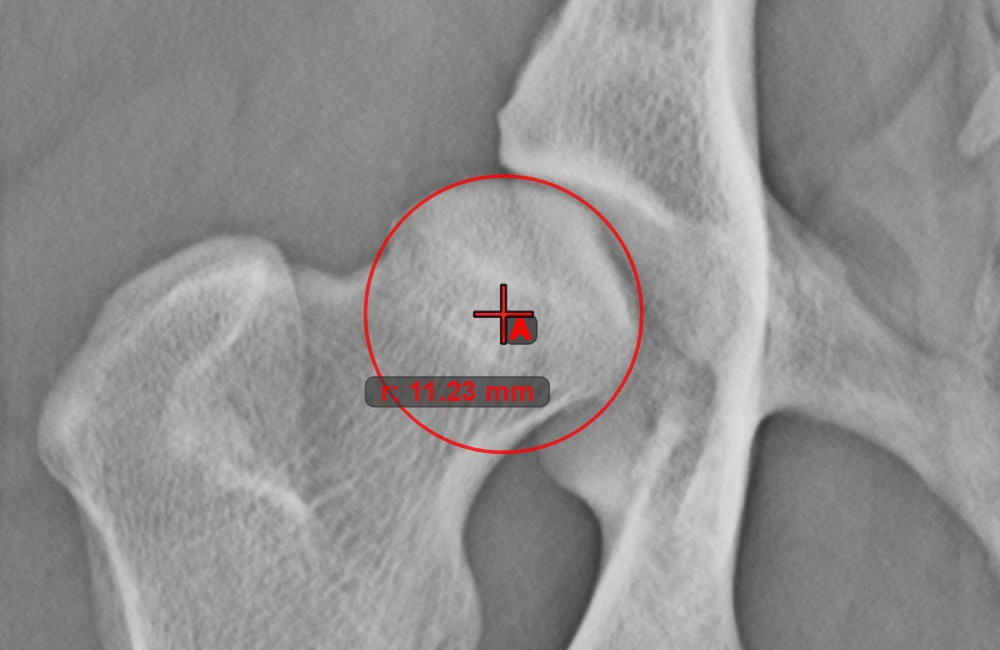

Kreis aus 3 Punkten¶

Das Werkzeug Kreis aus 3 Punkten ist eine einfache und effektive Möglichkeit, einen Kreis anhand von nur drei Punkten zu erstellen.

Beginnen Sie, indem Sie das Werkzeug aus der linken Symbolleiste auswählen und einer der verfügbaren Maustasten zuweisen. Setzen Sie die drei Punkte des Kreises oder wählen Sie die Punkte aus den in der Szene verfügbaren aus. Der Kreis wird automatisch basierend auf der Position der drei Punkte erstellt. Der Ursprung des Kreises wird stets mit O markiert. Der Radius des Kreises wird automatisch berechnet.

Ändern Sie die Position der drei Punkte, um den Radius des Kreises mit dem Werkzeug Objekt auswählen/verschieben zu ändern.